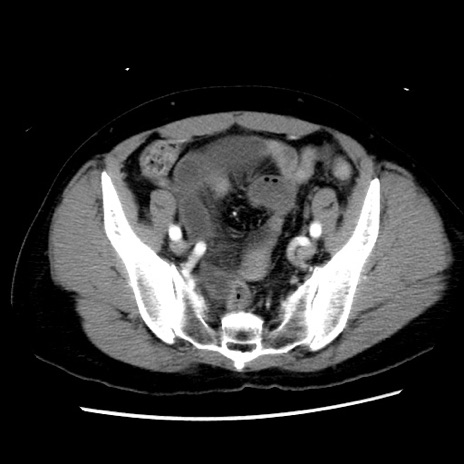

症例10(横断像)

【症例】 50歳代女性

【主訴】 腹痛

【現病歴】前日生レバーを食べた。今朝に排便あり。 昼前に突然発症の腹痛を生じ、当院救急外来を受診した。

【既往歴】 子宮筋腫にてで子宮全摘後

【身体所見】 意識清明、腹部:平坦、軟、下腹部やや左を中心に圧痛・反跳痛あり、筋性防御あり

【データ】WBC 7800、CRP 0.07